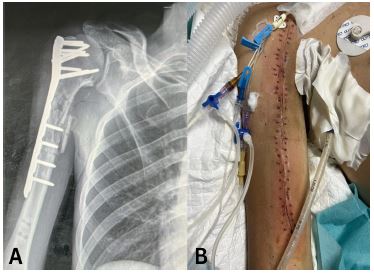

Case 3

A 22-year-old male presented with a traumatic brain injury, a right-sided haemothorax, and a Gustilo-Anderson Grade III open fracture of the right proximal humerus caused by a gunshot injury. The patient received intercostal tube drainage and underwent ORIF (Figure 3A), primary wound closure, and received a course of IV Ceftriaxone. He was admitted to the ICU for 3 weeks and the wound was found to have healed by week 2 (Figure 3B). Unfortunately, the patient failed trials of extubation and passed away on week 4.

Images are Not Display Check it

Figure 3: (A) Anteroposterior view radiograph of the comminuted fracture of the right proximal humerus with plate and nails visible in situ. (B) Clinical photograph of the healed wound.